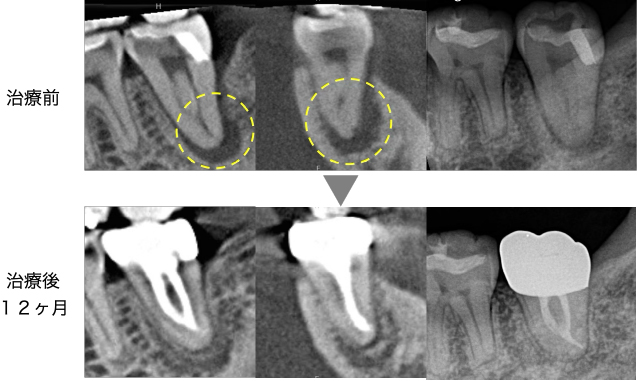

12ヶ月後のCT画像にて、元々大きく広がっていた骨の吸収が完全に再生していることが確認できました。症状も全くないとのことで、セラミッククラウンを装着して治療は終了となりました。

術後12ヶ月時点で根の先の骨も完全に再生しているため、今後もおそらく問題なく使用してもらえると思います。